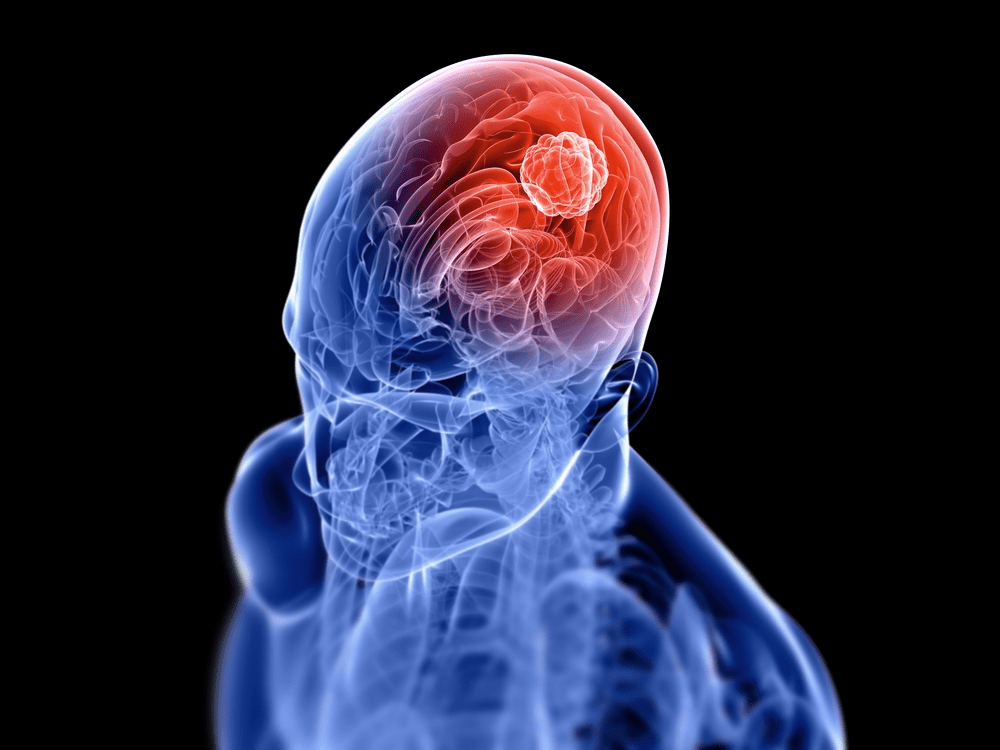

But what if your body has been whispering something you shouldn’t ignore? What if certain subtle signs are more important than they seem? Most early brain tumor symptoms can feel ordinary, which is exactly why they slip past unnoticed.

You’re about to discover eight early signs that many people overlook. Not to scare you, but to empower you. Because awareness is one of the simplest tools you can use to protect yourself.

Why Early Signals Matter More Than You Think

Your brain is incredibly delicate. Even tiny changes in pressure, swelling or nerve signals can cause unusual sensations throughout your body. These sensations might appear harmless at first.